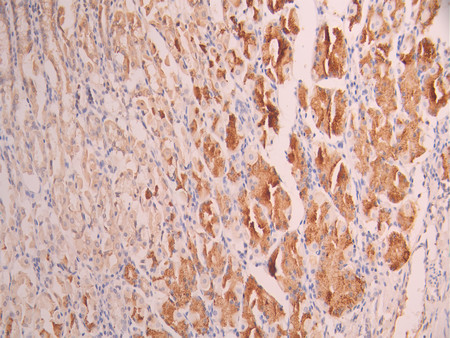

IHC image of CSB-RA906984A0HU diluted at 1:100 and staining in paraffin-embedded human liver cancer performed on a Leica BondTM system. After dewaxing and hydration, antigen retrieval was mediated by high pressure in a citrate buffer (pH 6.0). Section was blocked with 10% normal goat serum 30min at RT. Then primary antibody (1% BSA) was incubated at 4°C overnight. The primary is detected by a Goat anti-rabbit polymer IgG labeled by HRP and visualized using 0.05% DAB.